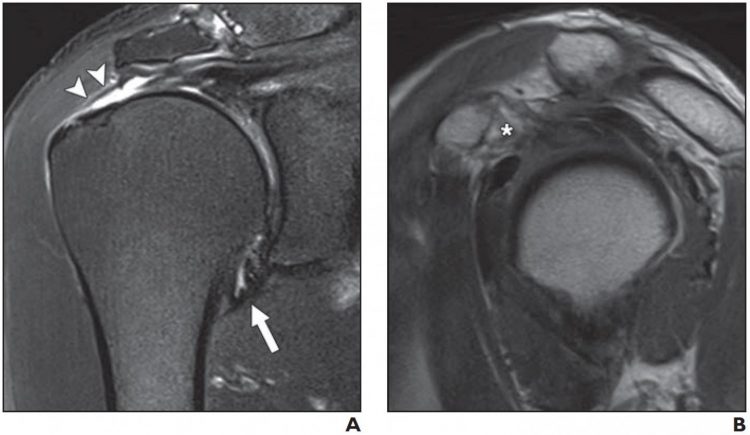

Two MRI findings–joint capsule edema and thickness at the axillary recess, specifically–proved useful in predicting stiff shoulder in patients with rotator cuff tears, according to an ahead-of-print article in the May issue of the American Journal of Roentgenology (AJR).

As Kim and colleagues wrote: “There was a significant, negative linear correlation between limited ROM at forward elevation and thickness of the joint capsule in the glenoid portion of the axillary recess (p = 0.018), external rotation and joint capsule edema in the humeral portion of the axillary recess (p = 0.011), and internal rotation and joint capsule edema in the glenoid portion of the axillary recess (p = 0.007).”

“This study is important,” Kim et al. noted, “because it is the first to highlight joint capsule abnormality on MRI as a factor associated with stiff shoulder in patients with full-thickness rotator cuff tears.”